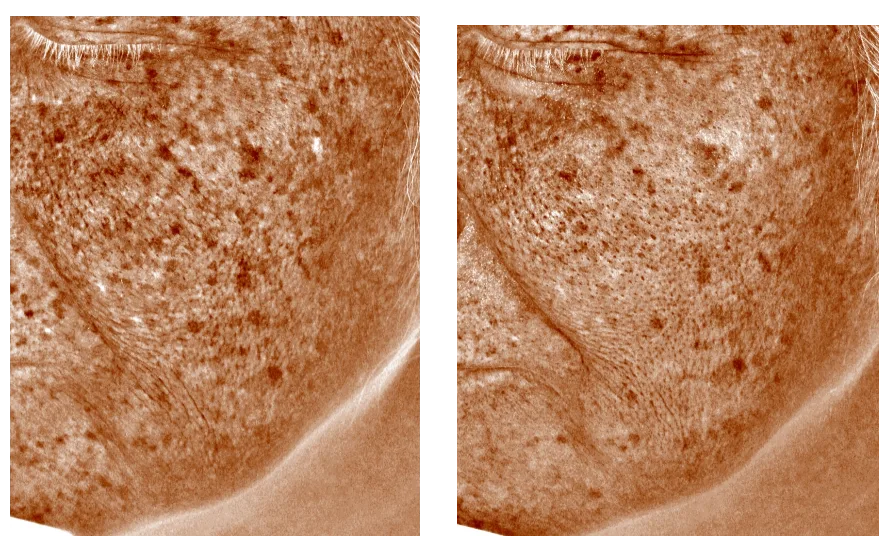

③レーザートーニング(5回コース4回施術後)

左頬の広範囲の肝斑です、一見あまり改善されていないように見えますが、シミモード撮影では頬の下の方と中心にシミが薄くなっています。

【リスク】熱傷・瘢痕・白抜け・水疱形成 ・炎症性色素沈着・肝班の悪化

【治療間隔】2週間間隔・5回コース

【施術料金】税込¥73,000円

【備考】治療効果には個人差があります。